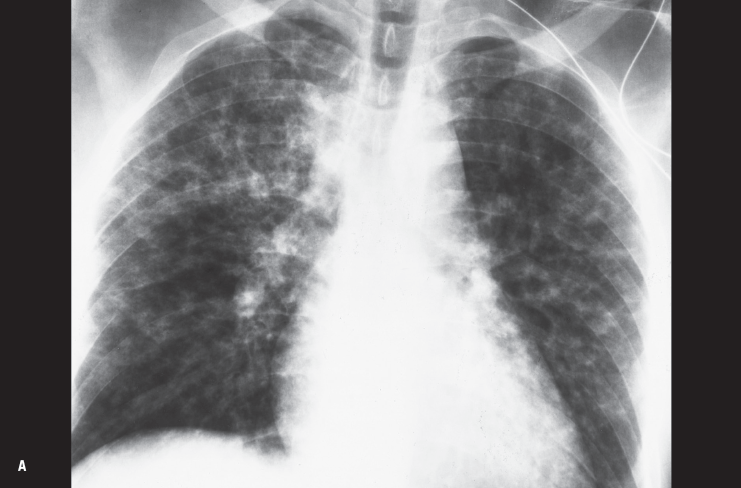

The patient’s temperature was 37.3°C (99.1°F). Her pulse was 110 beats per minute and respiratory rate, 22 breaths per minute. She appeared confused but in no apparent acute distress. Lung auscultation revealed bronchial breath sounds at the left base; she had an occasional moist cough. A chest film (seen here) showed lower left lobe opacity.

In this case, the patient’s chest film demonstrated a lower left lobe opacity, which was considered to be pneumonia in light of the acute onset of delirium and cough. She was treated with intravenous ceftriaxone and azithromycin. Blood cultures obtained on admission were positive for Streptococcus pneumoniae sensitive to penicillin. She improved after 3 days of intravenous antibiotics, and she continued therapy with oral azithromycin as an outpatient. Her chest film was normal 3 months later.